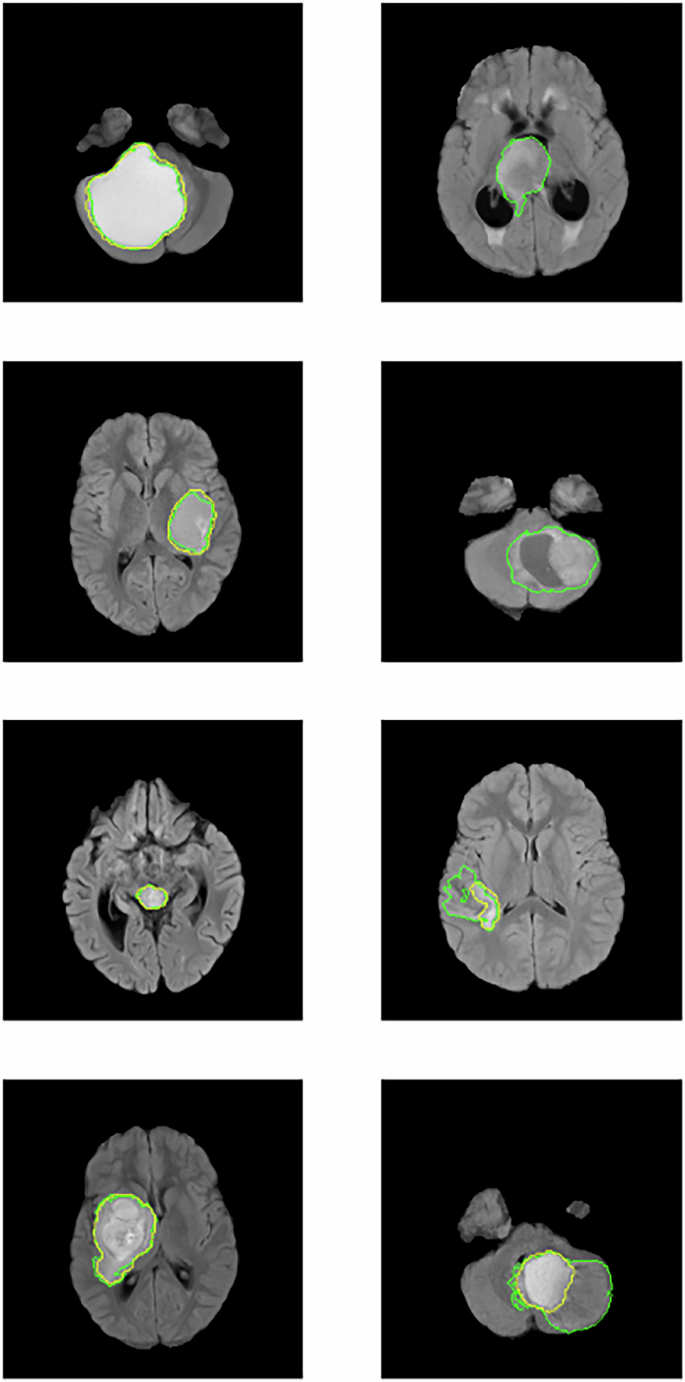

We also explored the potential for advanced DL architectures to accurately and reliably segment MRIs of patients with pLGGs. Previous PLGG segmentation studies have relied on CNN-based models19,23; we found that a modern architecture, based on the MedNext architecture, performed better. The MedNeXt model was designed using ConvNeXt27 layers, which combine the inherent inductive biases of CNNs with the ability of transformers to scale efficiently and capture long-range dependencies35. It appears that MedNeXt combines the best of CNNs and transformers; it was previously shown to outperform both CNNs and transformers for adult brain tumor segmentation35. Our results suggest MedNeXt is better at pediatric brain tumor segmentation, too. However, for some patients, segmentations were poor (Fig. 5), suggesting that automated segmentations are too unreliable for use in downstream tasks although they were sufficiently accurate to be helpful in pretraining. Although expert manual segmentations are currently considered the gold standard, they pose practical challenges as classification model inputs due to known inter- and intra-rater variability, as well as scalability concerns. Variability in model inputs may reduce model reliability and harm clinician confidence when predictions are sensitive to subtle differences in input delineations.

Notably, for the two topmost cases in the right column, the segmentation is completely off, with no tumor identified at all in the slice depicted. A downstream classification model will struggle to identify the genetic status of a tumor accurately if the automated segmentation model it depends on does not correctly identify the tumor.